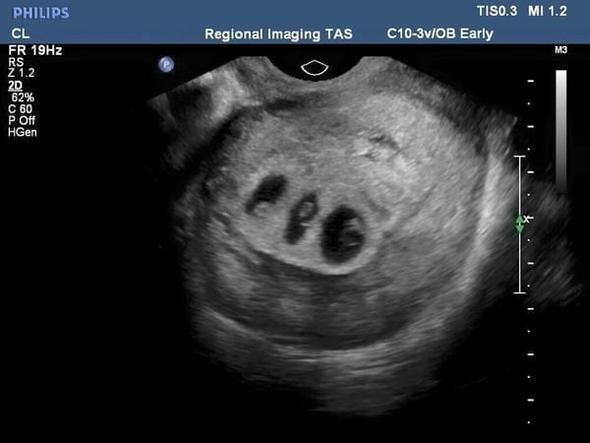

Chloe ilk kez ultrasona girmiyordu. Bu kez karnı inanılmaz büyüktü. Orada göreceklerini tahmin bile edemezdi. Facebook’ta “Doktor önce ‘Şurada bir bebek görüyorum. Bir dakika şurada da bebek var’ dedi. Ben de ‘İkizlerim mi olacak?’ diye sordum” dedi.

Meğerse Chloe’nin üçüzleri olacakmış.